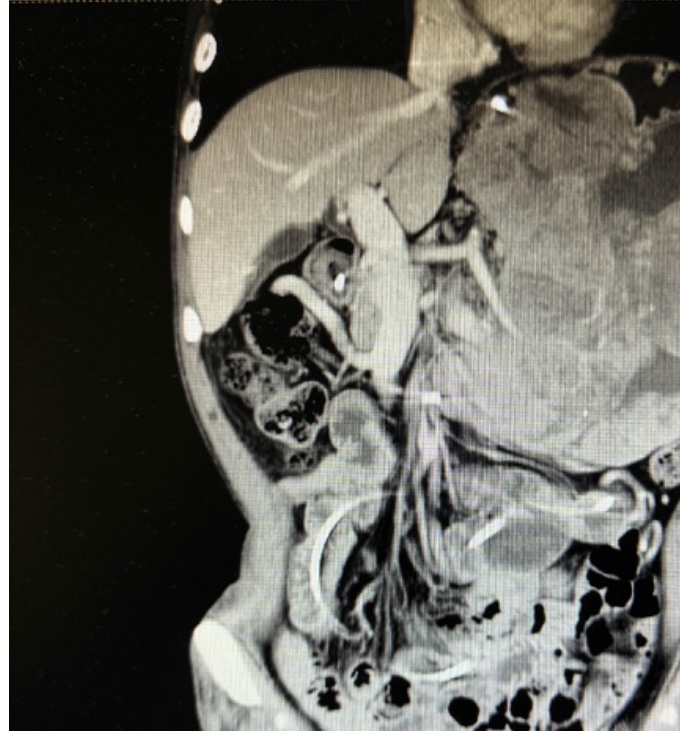

张翼主任医师接诊后,第一时间牵头对患者进行全面评估,经影像检查进一步确认:肿瘤体积巨大且与脾动脉粘连紧密,术中稍有不慎就可能引发致命性大出血,手术难度远超常规胃肠肿瘤手术。为最大程度降低风险,张翼教授先后多次组织全院大会诊,联合麻醉科、输血科、重症医学科、影像医学科等多学科专家反复推演手术方案,从手术入路的选择、血管保护的细节,到术中输血预案、术后并发症防控,每一个环节都制定了详尽的应对策略。

患者术前影像资料

经过严格的术前准备和周密的计划,在胃肠外科李小荣主任医师、肝胆胰外科余枭主任医师的指导下,由胃肠外科张翼主任医师、郭一航副主任医师团队联合肝胆胰外科孙吉春副主任医师的多学科团队,成功为患者实施了腹腔巨大肿瘤及多脏器联合切除手术。术中,当团队切开腹腔后,巨大肿瘤与脾动脉的粘连程度远超术前预判,解剖结构模糊不清;随着分离操作的推进,患者在术中出血量逐渐增加,甚至高达 2000ml。面对紧急情况,张翼主任医师团队始终沉着冷静,凭借数十年积累的外科经验与精准的操作技巧,小心翼翼地剥离肿瘤与血管的粘连组织,避开每一处关键神经与分支血管,一步步 “拆解” 肿瘤对脾动脉的包裹。经过数小时的高强度手术,团队最终将完整的巨大肿瘤完整切除,手术顺利结束。